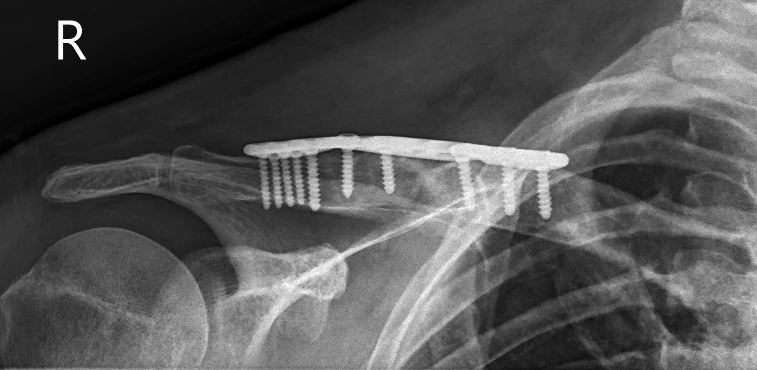

Post op xray 1 of clavicle  open reduction and internal fixation of the right clavicle with iliac crest bone grafting

Post op xray 1

At six-month review, radiographs demonstrated solid fracture union with restoration of clavicular alignment. Clinically, he had achieved full range of motion, complete resolution of deformity, and was entirely pain-free.